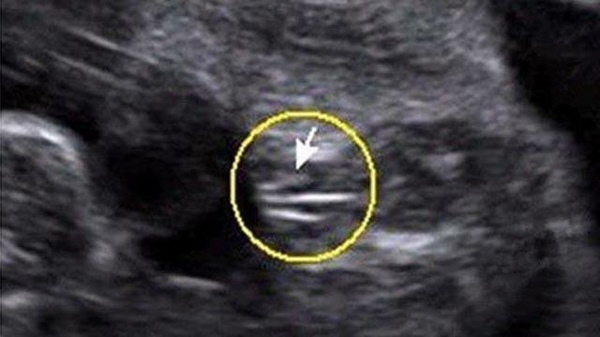

B超上三條線可能是女孩

1、三條線

上圖大致代表女寶的生殖器結(jié)構(gòu),上面有類似于線條的一杠,這就是女寶胎兒的外生殖器結(jié)構(gòu)了,也就是我們所說的大小陰唇,有的時(shí)候b超看到是一條線,大多時(shí)候是三條,有這一點(diǎn),女寶就更好確認(rèn)了。孕周大了之后,這個(gè)時(shí)候性別特征不僅很明顯,而且非常清晰好分辨,看男女基本都是十有八九的事情;